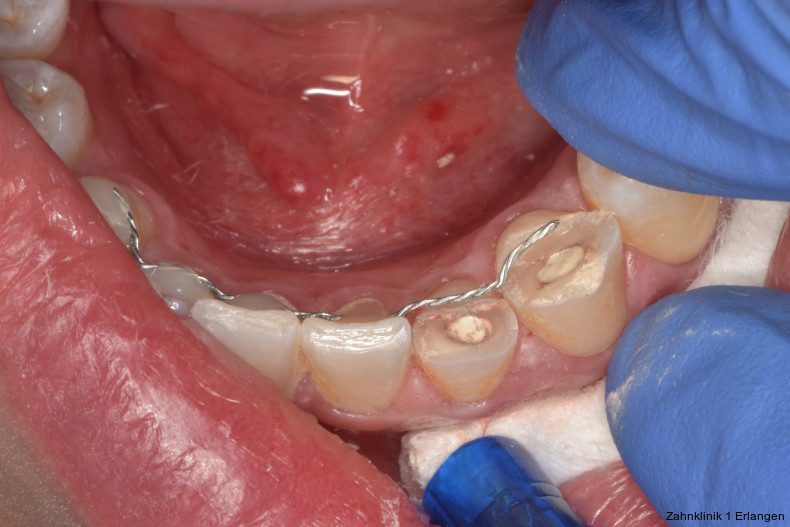

Versorgung von Dislokationsverletzung

Bei ausgeprägten Dislokationsverletzungen stellt die Schädigung des Parodonts die dominierende Verletzung dar, die auch zu Spätfolgen und Komplikationen führen kann. Verletzungen des Endodonts sind im Hinblick auf den Zahnerhalt vergleichsweise unbedeutender, da die Wurzelkanalbehandlung eine Infektion relativ sicher verhindern oder beseitigen kann. Die Erstversorgung schließt im Wesentlichen die Repositionierung und Schienung zur Ruhigstellung der betroffenen Zähne ein.3 Spätestens ab einer Positionsveränderung von 2 mm ist bei Zähnen mit abgeschlossenem Wurzelwachstum sicher von einem irreparablen Schaden der Pulpa auszugehen.2 Wichtig ist es, zeitnah, in der Regel während der Schienungsdauer, die Wurzelkanalbehandlung einzuleiten, um eine bakterielle Besiedelung des Wurzelkanals zu verhindern. Dabei reicht es zunächst aus, den Zahn zu eröffnen, desinfizierend zu spülen und eine medikamentöse Einlage einzubringen. Wird dies unterlassen, entwickeln sich bei entsprechender parodontaler Schädigung infektionsbedingte Resorptionen, die rasch fortschreiten und innerhalb relativ kurzer Zeit bis zum Zahnverlust führen können.